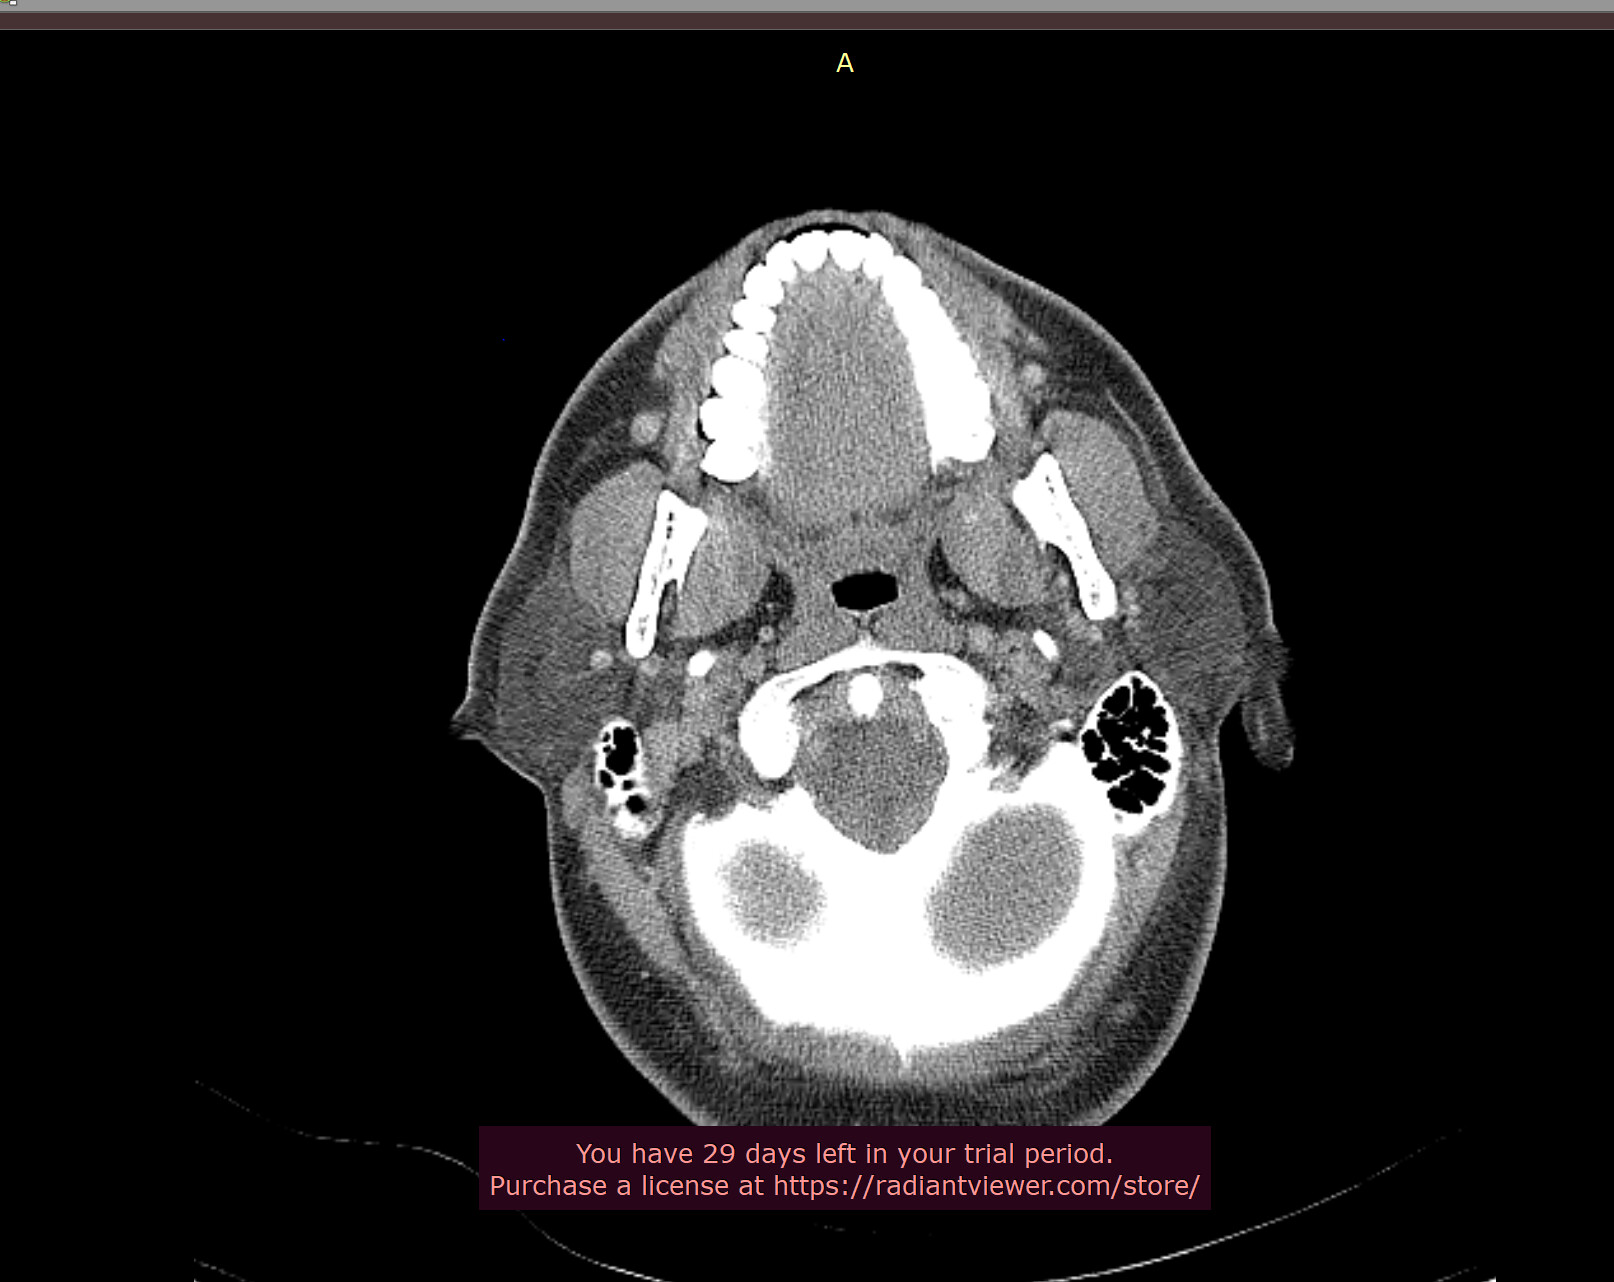

Hey all thanks, will take a look at the video shortly, in the meantime here’s the axial view, I think.

Thanks! I’m digging in a little more and have a few more shots.

Wow your right styloid/stylohyoid ligament is almost as long as it can get!! Your left side the styloid is around normal length and then there is a length of normal stylohyoid ligament, followed by a long pocket of calcified stylohyoid ligament.

Crazy styloids! It looks like on the 3D images that there’s a reasonable gap between the styloids & the C1 process, but sometimes it can be more obvious on the axial images, it could be that the digastric muscle is causing compression as @TML saw…